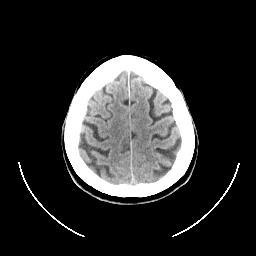

CT Study #1 -- Slice #24